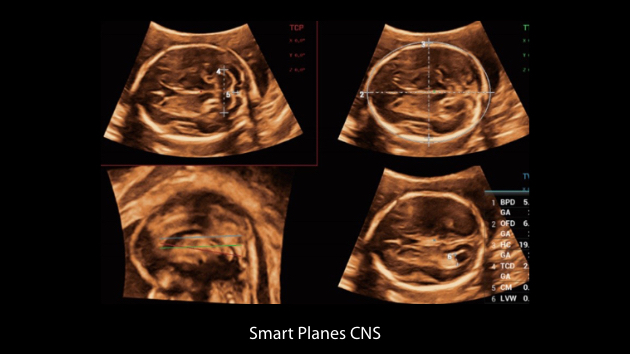

Nuewa I9? ??? ???? ?? ??? ?? ??? ???? ?? ??? ???? ???? ??? ?????. ??? ??? ??? ?? ????? ?? ???? ???? ???? ???? ??? ???? ??? ??? ???? ??? ???? ??? ?? ?????.

ZST+ ???? ???? ??? ???? ??? ?????. ??? ????? ??? ? ???? ?? ??? ?? ????? ?????. ?? ???, ?? ???, ?? ??? ?? ?? ?? ??? ??? ???? ???? ??? ?? ??? ?? ???? ?? ??? ?? ??? ?????.